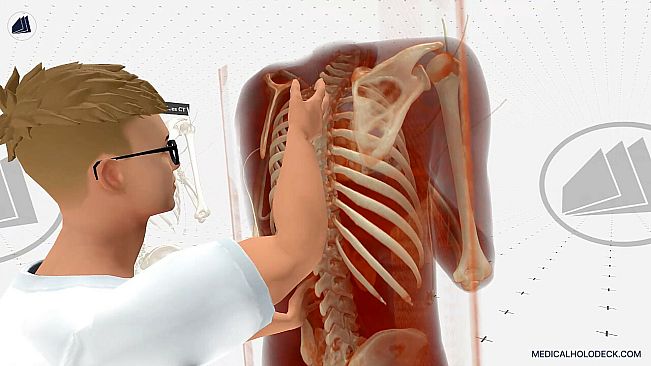

Experience medical education in virtual reality. Explore detailed 3D human dissections and 3D anatomy models. Automatically segment CT scans with AI, and exercise surgeries in an immersive environment.

Developed for future doctors, surgeons, nurses, and medical students, Medicalholodeck provides an immersive 3D environment to interact with patient data, medical imaging, high-res anatomical dissections, and anatomy models.

Study Anatomy

Explore human anatomy in full 3D, from any angle and scale. Examine pathologies in detail and deepen your medical understanding.

Anatomy Master 2 – Detailed male and female 3D models for anatomy education.